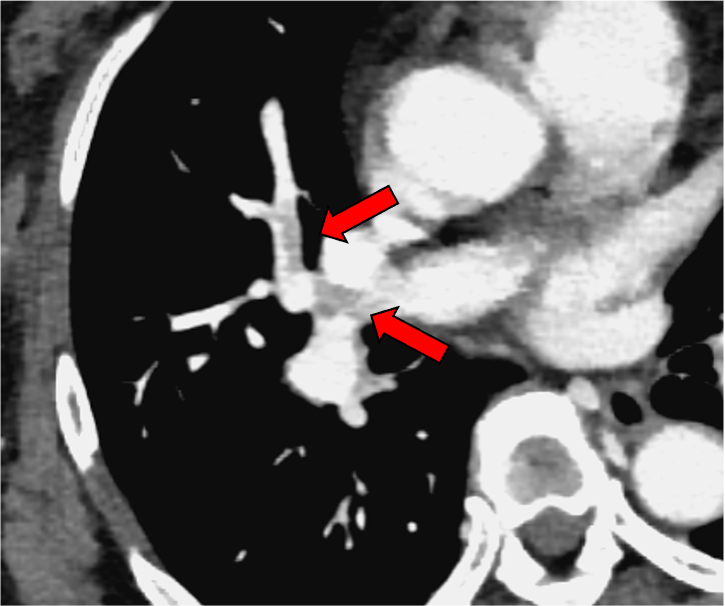

乳癌化学療法の治療効果判定CTに映り込んでいた偶発肺塞栓。通常の門脈相120kVp画像では肺動脈の造影効果が乏しく、血栓を見逃してしまうリスクがある。これに対して、Dual-energy CTの仮想単色X線エネルギー画像(MonoE 40keV)では肺動脈のヨードコントラストが劇的に向上しており、造影欠損を示す肺塞栓を高い確信度で診断可能である。本症例では肺動脈プロトコルでの再撮影を行うことなく、速やかに抗凝固療法が開始され、その後、血栓の消失が確認された。

CT技術や撮像プロトコル設定について